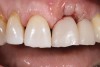

Following sufficient time for osseointegration and maturation of the soft tissue, the peri-implant architecture can be evaluated. Because the initial emergence profile was quite narrow, there may be an excess of soft tissue (which is rather desirable around an implant) (Figure 14). The mesio-distal width of the tooth may also be deficient at the gingival aspect. At this time, the restoration is removed and the deficient areas are augmented with composite or acrylic. Open gingival embrasures should also be closed, if desired. When the restoration is reinserted onto the implant the tissue will blanch, indicating that the increased emergence volume is placing pressure and reducing blood flow. The tissue will migrate away from this pressure, but it is unknown how far and how quickly this will occur.

Any modifications to the emergence profile intended to affect the soft tissue should be allowed to remain in place for 4 to 6 weeks (Figure 17). This will give the tissues sufficient time to mature and adjust.

Clinicians cannot fully predict how peri-implant tissues will respond to treatment and modifications, nor can they completely understand what the patient is expecting. Use of a provisional restoration and careful manipulation of the emergence profile provides in-situ testing of the patient’s biology, adaptation, and expectations. Changes to the position of the soft tissue can be tested, proven, and modified as needed and to the extent possible given inherent patient factors. When all of the parties involved are satisfied with the results in the provisional, the final impression is made (preferably with customized copings) and the technician will now have a comprehensive blueprint to follow.

Fig 17. Creation of the final soft-tissue architecture during the provisional stage provides a superior level of predictability and will minimize the chance of tissue changes following placement of the definitive restoration.